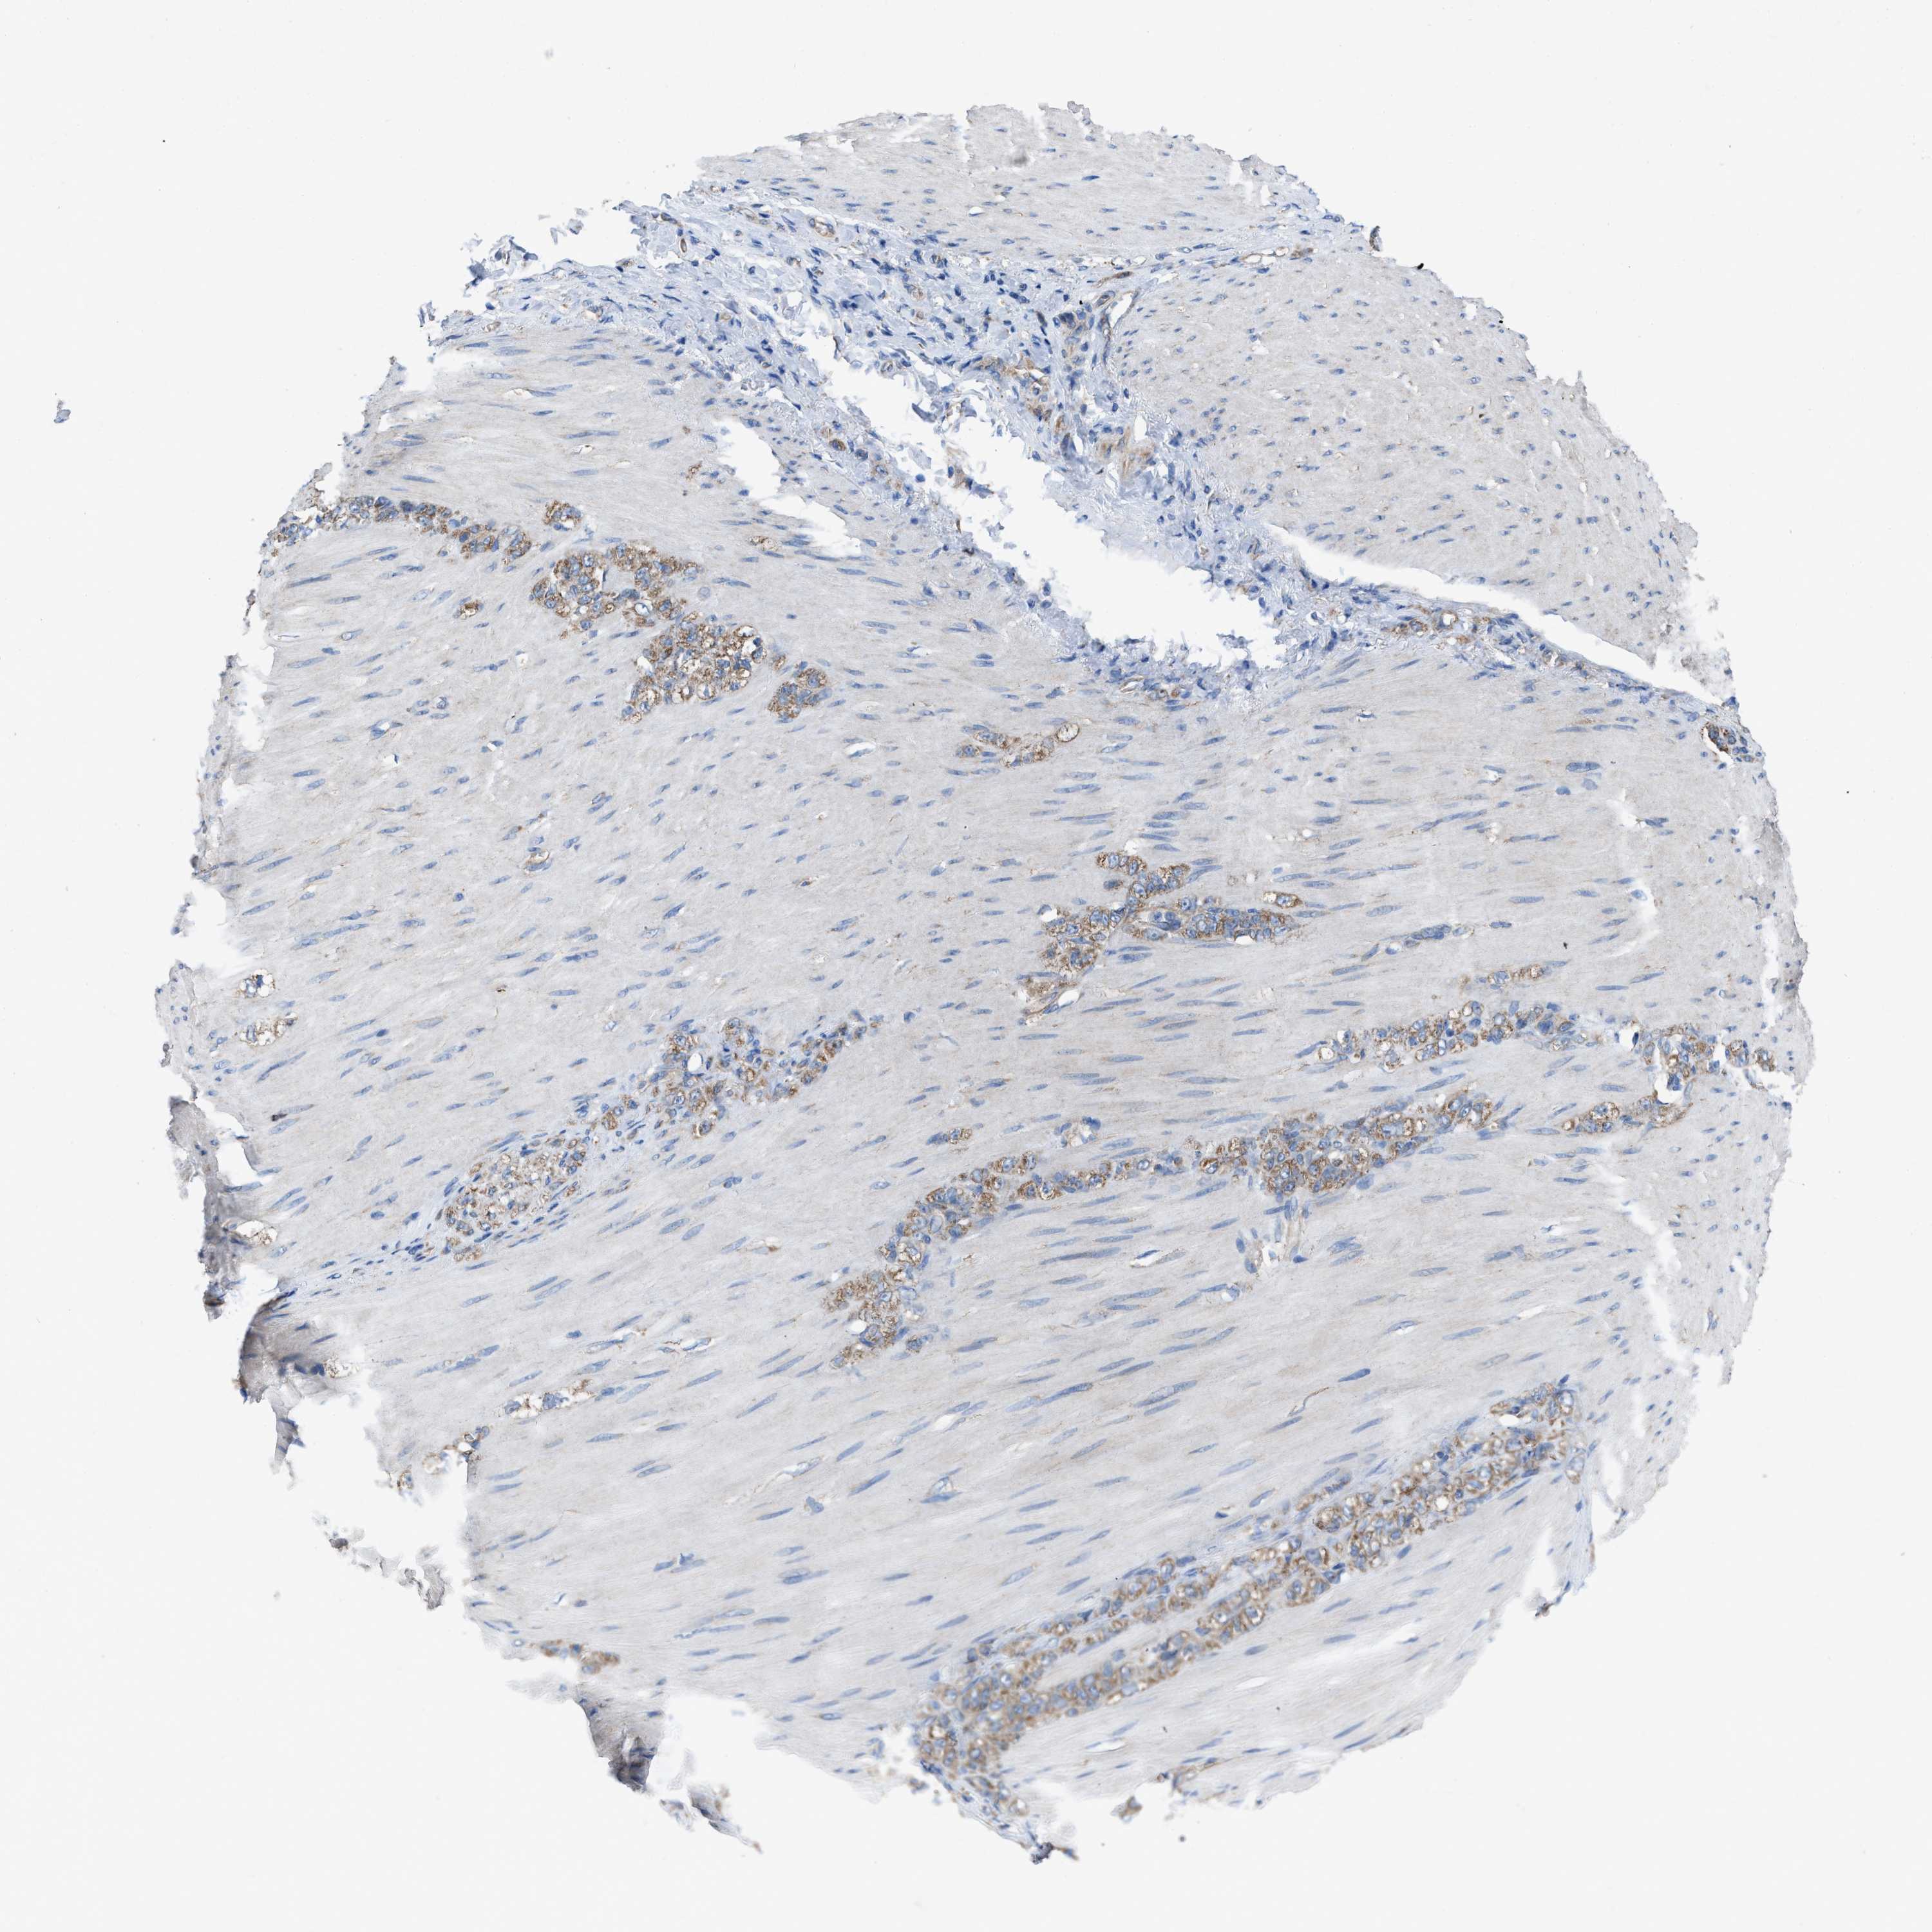

STOMACH CANCER - Protein expressioni

A mouse-over function shows sample information and annotation data. Click on an image to view it in a full screen mode. Samples can be filtered based on level of antibody staining by selecting one or several of the following categories: high, medium, low and not detected. The assay and annotation is described here.

Antibody stainingi

Antibody staining in the annotated cell types in the current human tissue is reported as not detected, low, medium, or high, based on conventional immunohistochemistry profiling in selected tissues. This score is based on the combination of the staining intensity and fraction of stained cells.

Each image is clickable and will lead to virtual microscopy that enables deeper exploration of all samples and also displays staining intensity scores, fraction scores and subcellular localization as well as patient and tissue information for each sample.

Antibody HPA019179

Staining

High

Medium

Low

Not detected

Intensity

Strong

Moderate

Weak

Negative

Quantity

>75%

75%-25%

<25%

None

Location

Nuclear

Cytoplasmic/membranous

Cytoplasmic/membranous,nuclear

Adenocarcinoma, NOS